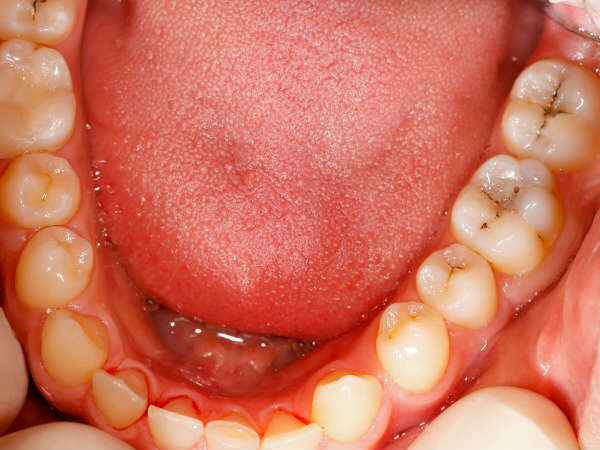

എന്നാല് പുകവലിക്കാത്തവരില് ഉണ്ടാവുന്ന ക്യാന്സറിന് കാരണം എന്തൊക്കെയെന്ന കാര്യം അറിഞ്ഞിരിക്കേണ്ടതാണ്. വായില് കാണപ്പെടുന്ന ബാക്ടീരിയകളുടെ തരവും അവയും പുകവലിക്കാത്തവരില് ശ്വാസകോശ അര്ബുദ സാധ്യതയുമായി ബന്ധപ്പെട്ടിരിക്കാമെന്ന് തോറാക്സ് ജേണലില് ഓണ്ലൈനില് പ്രസിദ്ധീകരിച്ച ഒരു പുതിയ പഠനം പറയുന്നു. ഇതിനെക്കുറിച്ച് കൂടുതല് അറിയുന്നതിന് വേണ്ടി നമുക്ക് വായിക്കാവുന്നതാണ്. വായിലുണ്ടാവുന്ന ചില പ്രത്യേക ബാക്ടീരിയകളാണ് നിങ്ങളില് പ്രശ്നങ്ങള് ഉണ്ടാക്കുന്നത്. ഇതിനെക്കുറിച്ച് കൂടുതല് അറിയുന്നതിന് വേണ്ടി വായിക്കാം.

ഗവേഷകരുടെ അഭിപ്രായത്തില്, ഈ ഉയര്ന്ന അപകടസാധ്യത കുറച്ച് സ്പീഷിസുകളുടെ സാന്നിധ്യവും വായില് ഒരു പ്രത്യേക തരം ബാക്ടീരിയകളുടെ ഉയര്ന്ന സംഖ്യയുമാണ് ക്യാന്സറിന് കാരണം എന്ന് പറയുന്നത്. വായില് കാണപ്പെടുന്ന ബാക്ടീരിയയുടെ തരവും അളവും (മൈക്രോബയോം)തല, കഴുത്ത്, പാന്ക്രിയാസ് ക്യാന്സര് എന്നിവയുള്പ്പെടെയുള്ള വിവിധ അര്ബുദങ്ങളുടെ അപകടസാധ്യതയുമായി ബന്ധപ്പെട്ടിരിക്കുന്നു. ശ്വാസകോശത്തിലേക്കുള്ള ബാക്ടീരിയയുടെ പ്രവേശന കവാടമാണ് എപ്പോഴും വായ. അതുകൊണ്ട് തന്നെ ഇതിന് പരിഹാരം കാണുന്നതിന് വേണ്ടി നമുക്ക് ചില കാര്യങ്ങള് ശ്രദ്ധിക്കാവുന്നതാണ്. പഠനത്തെക്കുറിച്ച് കൂടുതല് അറിയുന്നതിന് വേണ്ടി വായിക്കൂ.